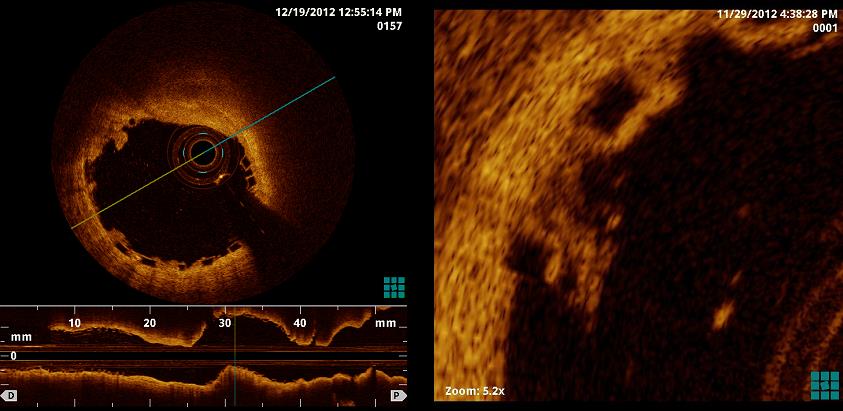

Durch die OCT können Koronarplaque mit höherer Sensivität und Spezifität erkannt und deren Beschaffenheit interpretiert werden. Durch die hohe Auflösung der OCT können im Besonderen komplexe Bifurkationsstenosen, Stenosen des Hauptstamms, oder Stenosen an mehreren Koronararterien beurteilt werden. Auch die Beurteilung der Lage und Positionierung eines Stents ist nach Implantation in hoher bildlicher Auflösung möglich und ist hier von besonderer Bedeutung.

Neuerdings wird in der Medizinischen Klinik I am Universitätsklinikum Gießen die neuartige dreidimensionale - Echtzeitdarstellung der OCT eingesetzt. Hierdurch werden 360°-Panoramaansichten des Gefäßes möglich und die Stentimplantation kann noch präziser geplant und optimiert werden. Die 3-D OCT Rekonstruktion ermöglicht eine besonders realitätsnahe 3D-Darstellung der Koronararterien.

Mit dem Einsatz einer speziellen und innovativen Software können die Messung der „fraktionellen Flussreserve“ (FFR) mit der intravaskulären „optischen Köharenztomografie“ (OCT) zusammengeführt werden. Dies erlaubt eine individuell an den Patienten angepasste Therapie, und die Koronarintervention wird insgesamt weiter optimiert.